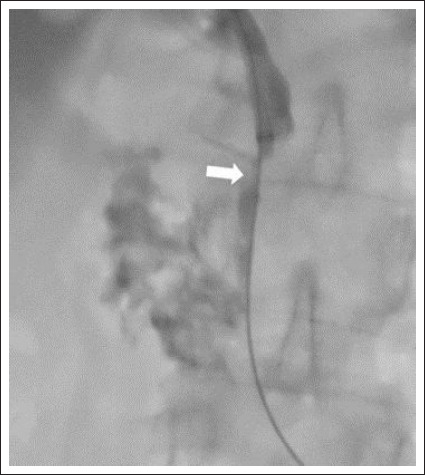

Materials and methods: This retrospective, single-center study was conducted between January 2022 and April 2023, involving a total of 16 patients. Of the patients, 10 were male (62.5%), and 6 were female (37.5%). The average age of the patients was 68.1±8. All patients underwent the procedure using an endobiliary biopsy brush under ultrasound and fluoroscopic guidance.

Results: Technical success was achieved in all patients (100%). Cell detection was not observed in biopsy samples from 2 patients (12.5%), resulting in a diagnostic success rate of 87.5%. Access was made to the right biliary system in 14 patients (87.5%) and to the left biliary system in 2 patients (12.5%). Biopsy locations included the common bile duct in 12 patients (75%), hepatic hilum in 2 patients (12.5%), and bilioenteric anastomosis line in 2 patients (12.5%). The mean fluoroscopy time was 16.2±7.1 minutes. The average radiation dose was 660±370 mSv. Pathological diagnosis revealed malignancy in 8 patients (50%) and benign findings in 6 patients (37.5%). Liver abscess requiring drainage developed in 2 patients (12.5%).

Abstract Image